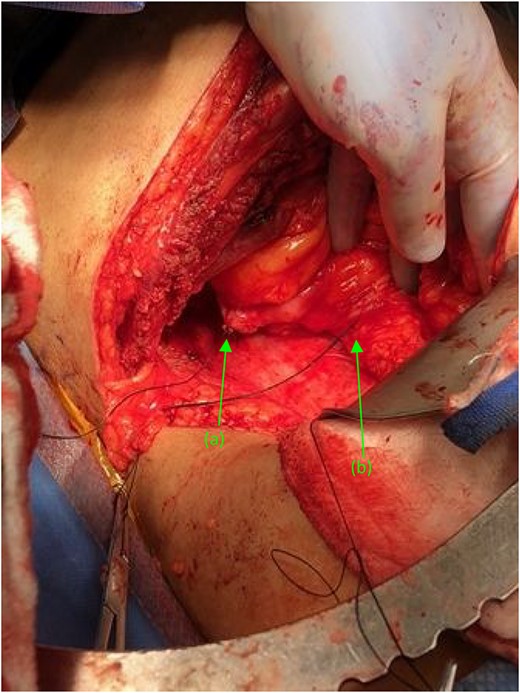

Two suture tagged fistulas status post fistulectomy and debridement to their base, entering the (a) second and (b) third portions of the duodenum, status post nephrectomy.

(a) Repaired duodenal defect where the (first) fistula previously entered the second portion of the duodenum, status post fistulectomy and stump closure. (b) Second fistula indicated by suture tags status fistulectomy and trimming to the base of the fistulous tract, near its entry point at the third portion of the duodenum.